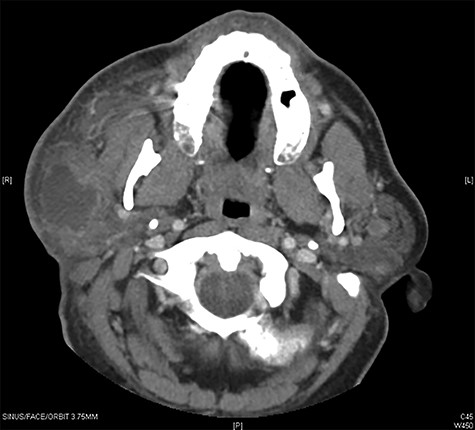

(a) Maxillofacial Axial CT with contrast showing multiple bilateral parotid gland lesions demonstrating internal enhancing septations with the largest lesion located in right parotid tail, measuring 1.9 x 2.1 cm and (b) associated PET CT scan showing bilateral hypermetabolic parotid lesions measuring up to a maximum standardized uptake value (SUV) of 10.0 on the left and 9.0 on the right.

The patient presented 6 months later with progressive bilateral cheek swelling, more significant on the right side. Repeat CT revealed multiple bilateral parotid gland lesions with the largest located within the right parotid tail (Fig. 2a). Positron emission tomography (PET) scan was ordered to rule out other diagnostic considerations including primary parotid tumors such as Warthin’s tumor or non-Hodgkin lymphoma, or secondary malignancy. Bilateral hypermetabolic parotid lesions were identified along with diffuse bilateral cervical adenopathy (Fig. 2b). Findings suggested bilateral BLEC which raised suspicion for a potential immunosuppressive state. An HIV panel was performed with a positive result. The patient underwent initial local aspiration and drainage to palliate his symptoms of cheek discomfort and treatment for HIV was discussed. Patient has since been placed on HIV medication for management and his bilateral cysts and lymph nodes have reduced in size at follow-up visits with no signs of further recurrence.